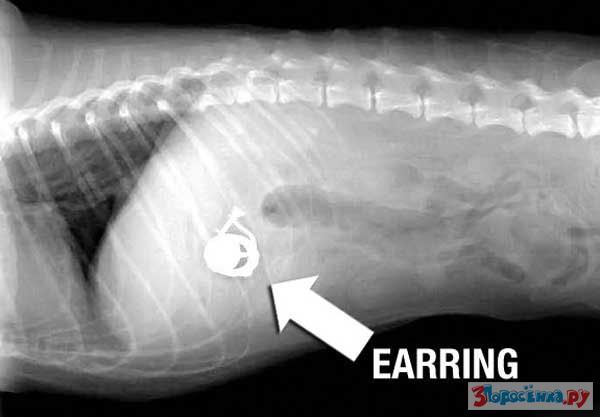

Нет ничего не перевариваемого

Некоторые собаки видимо полагают что их желудок способен переварить все на свете.